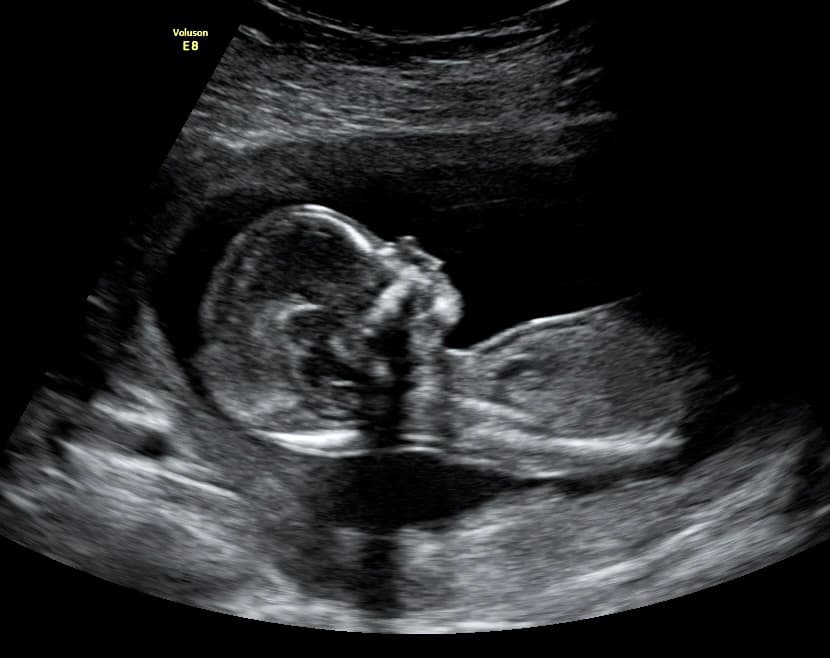

At Magnolia Fetal Imaging, we provide a warm, relaxing environment where you can bond with your baby through advanced 3D/4D & HD ultrasound technology. Our studio focuses on capturing precious keepsake moments for families — gender reveals, early looks, and high‑definition images you will cherish for a lifetime.

All sessions are non‑diagnostic and designed purely for bonding and keepsake entertainment.